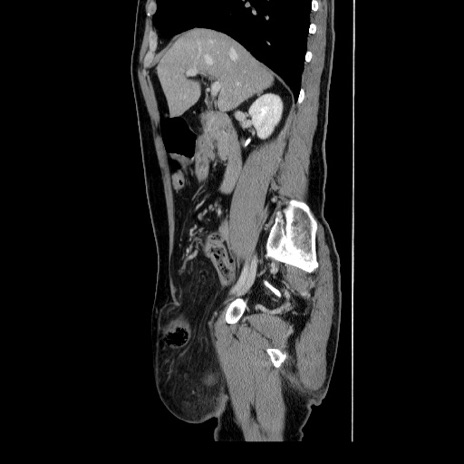

症例34(矢状断像)

【症例】60歳代 男性

【主訴】右鼠径部膨隆

【現病歴】1年程前より右鼠径部膨隆あり。自己にて還納可能だったため放置していた。3時間前より右鼠径部の脱出を認め、還納困難となり受診。

【身体所見】右鼠径部に小児頭大の膨隆あり。弾性硬であり、用手還納は困難。左鼠径部にも膨隆を認める。脱出はなし。